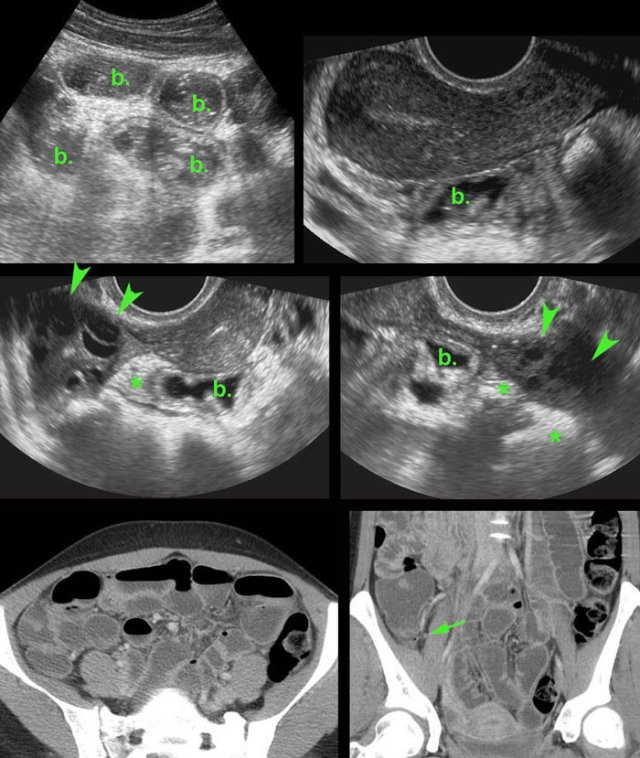

PID case 4

These images are of a very ill, painful young woman with generalized peritonitis and a CRP of 250, clinically suspect for perforated appendicitis.

US showed aperistaltic small bowel (b.).

The appendix

was not visualized.

TVUS showed a normal uterus and normal ovaries (arrowheads), which were surrounded by hyperechoic tissue (*).

CT confirmed the paralytic ileus and showed a normal appendix (arrow).

PCR was positive for gonorrhoea.